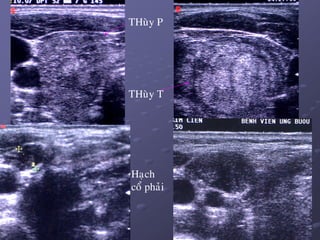

THuøy P

THuøy T

Haïch

coå phaûi

 Ñaëc ñieåm haïch di caên: maát hình baàu duïc, thöôøng hình

troøn, khoâng coøn roán haïch echo daày ôû vuøng trung taâm duø

haïch kích thöôùc nhoû. Ñoâi khi haïch coù caáu truùc echo daày

hôn cô, ñoàng nhaát, hay hoaïi töû, coù theå coù vi voâi hoùa trong

haïch. Ñoâi khi haïch mang hình aûnh gioáng nhö nhaân ung

thö nguyeân phaùt cuûa TG.